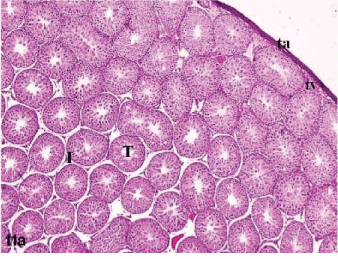

Figure 11a: a)Photomicrograph of a section in testis of control albino rat aged 7 weeks (group IIa) showing capsule of thick dense tunica albuginea (ta) and thin tunica vasculosa (tv) surrounding testicular tissue. The seminiferous tubules (T) appear closely packed with the interstitial tissue (I) in between.